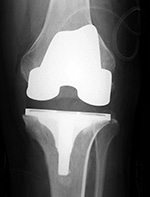

| 68 year-old woman treated for severe left knee osteoarthritis |

Note the large distal femoral box. There is a surgical drain in the suprapatellar space. |